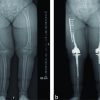

A one year and four months old male child presented with preaxial polydactyly of the right foot and dysplastic tibia associated with shortening and varus deformity in the right leg and foot. On examination the child was found to have normal mental and physical milestones. Obstetric history of the mother revealed no previous history of abortion. No history of any previous pregnancy. She was a primigravida with the first child being the present one with no siblings. The child was born from a full term pregnancy with caesarean for pregnancy induced hypertension. There was no history of consanguineous marriage in the family. On examination the child had a varus deformity in the right leg with a shortening of 5cm (Figure 1). The right leg as maintained in an attitude of flexion at the knee. Extension was possible actively with grade 3+ power in the right knee. Active flexion was possible up to 100 degrees. Complete range of movements possible at the hip however the ankle was fixed in a rigid equinovarus position. No instability was associated at the knee or ankle. Radiographs relevealed a trapezoid tibia with preaxial polydactyl (Figure 2a, b). At the time of presentation the child was 1 year 3 months but unable to walk. Since the other milestones both physical and mental had progressed well, the child’s inability to walk was attributed to the deformity in the left foot and tibia associated with shortening. Other associated anomalies included a preaxial polydactyly at the right hand with an additional right thumb. The child had an undescended testis on the left side with an absent kidney on the right side as well as no testes on the right side.

Problem faced by the child at the time of presentation were mainly: shortening, severe varus deformity of the tibia and foot which were not passively correctible, preaxial polydactyly causing inability to wear footwear and also giving the foot a grotesque cosmetic deformity. Aim of surgery at this stage was to provide the child with a plantigrade foot, improve cosmosis and enable child to wear footwear. Surgical procedure: Surgery was performed under general anesthesia with intubation. Surgery involved two stages. The first part was removal of the preaxial polydactyly in the foot. This was performed with a racquet shaped incision in which the toes were removed with the metatarsals. This procedure did not include excision of the duplicated talus. Thus 2 metatarsals and 2 sets of phalanges were excised. The wound was then closed over the medial aspect. The second part of the surgery was correction of the varus deformity in the trapezoid tibia. This varus deformity was corrected by a lateral incision over the leg on the most prominent part of the tibia. This was also marked by a small dimple in the skin. The tibia was dissected out subperiostialy. Two guide wires were used to mark out a lateral closed wedge osteotomy. A fibular osteotomy was done with excision of 1 cm of fibula to allow correction to occur at the osteotomy site. Correction was achieved with a lateral closed wedge osteotomy held in place with a pair of K wires. Closure of the wound was done. Cast maintained for a period of 2 months till the osteotomy site healed completely. K wires removed at 4 weeks of cast change when check x-ray showed good healing at osteotomy site. Post operatively the child was given a supportive clam shell brace extending up to the thigh with a shoe raise. This facilitated the child’s ability to walk and run. It also was expected to maintain the correction achieved. At 2 years follow up there was recurrence of varus deformity (Figure 3 a, b, c). There was overgrowth of the fibula with prominence of the fibular head. However the child was walking and running with help of orthosis and parents refused to undergo corrective surgery. The patient was lost to follow and finally was traced back 5 years after corrective surgery. At this time the tibia vara had increased with ankle inversion and overgrowth of fibula, however ankle dorsiflexion was 90º and plantar flexion was 30º. There was a limb length discrepancy of 9 cm, however the child was able to walk and run with shoe raise (Figure 4 a, b, c). Knee quadriceps was grade 5 with no flexion deformity and full range of knee movements. At present again the child’s parents are not ready for corrective surgeries but promise to keep regular follow up.